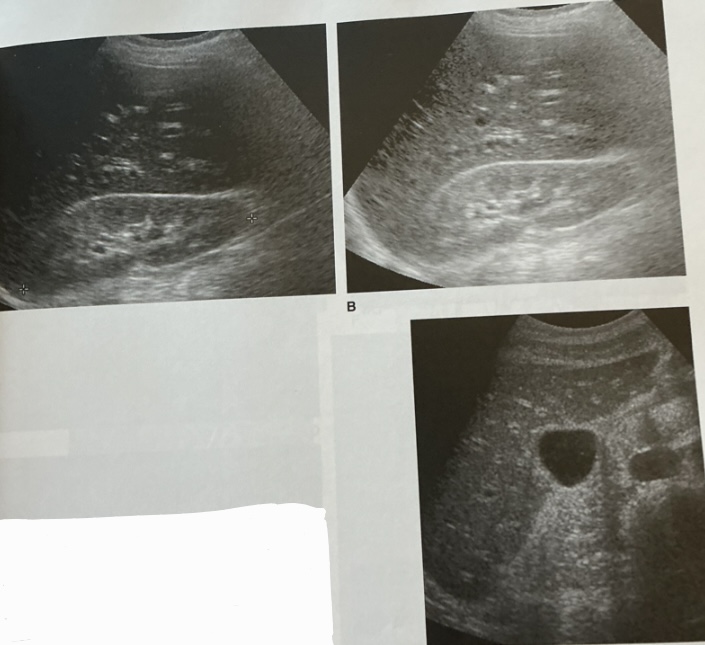

What is this sign? In what disease does this happen?

Starry star sign

acute hepatitis

Label this picture

what sign is it depicting

Why does this happen?

What sign does the hepatic veins normally depict?

Canadian moose sign

Dilatation from right heart failure

Playboy bunny sign